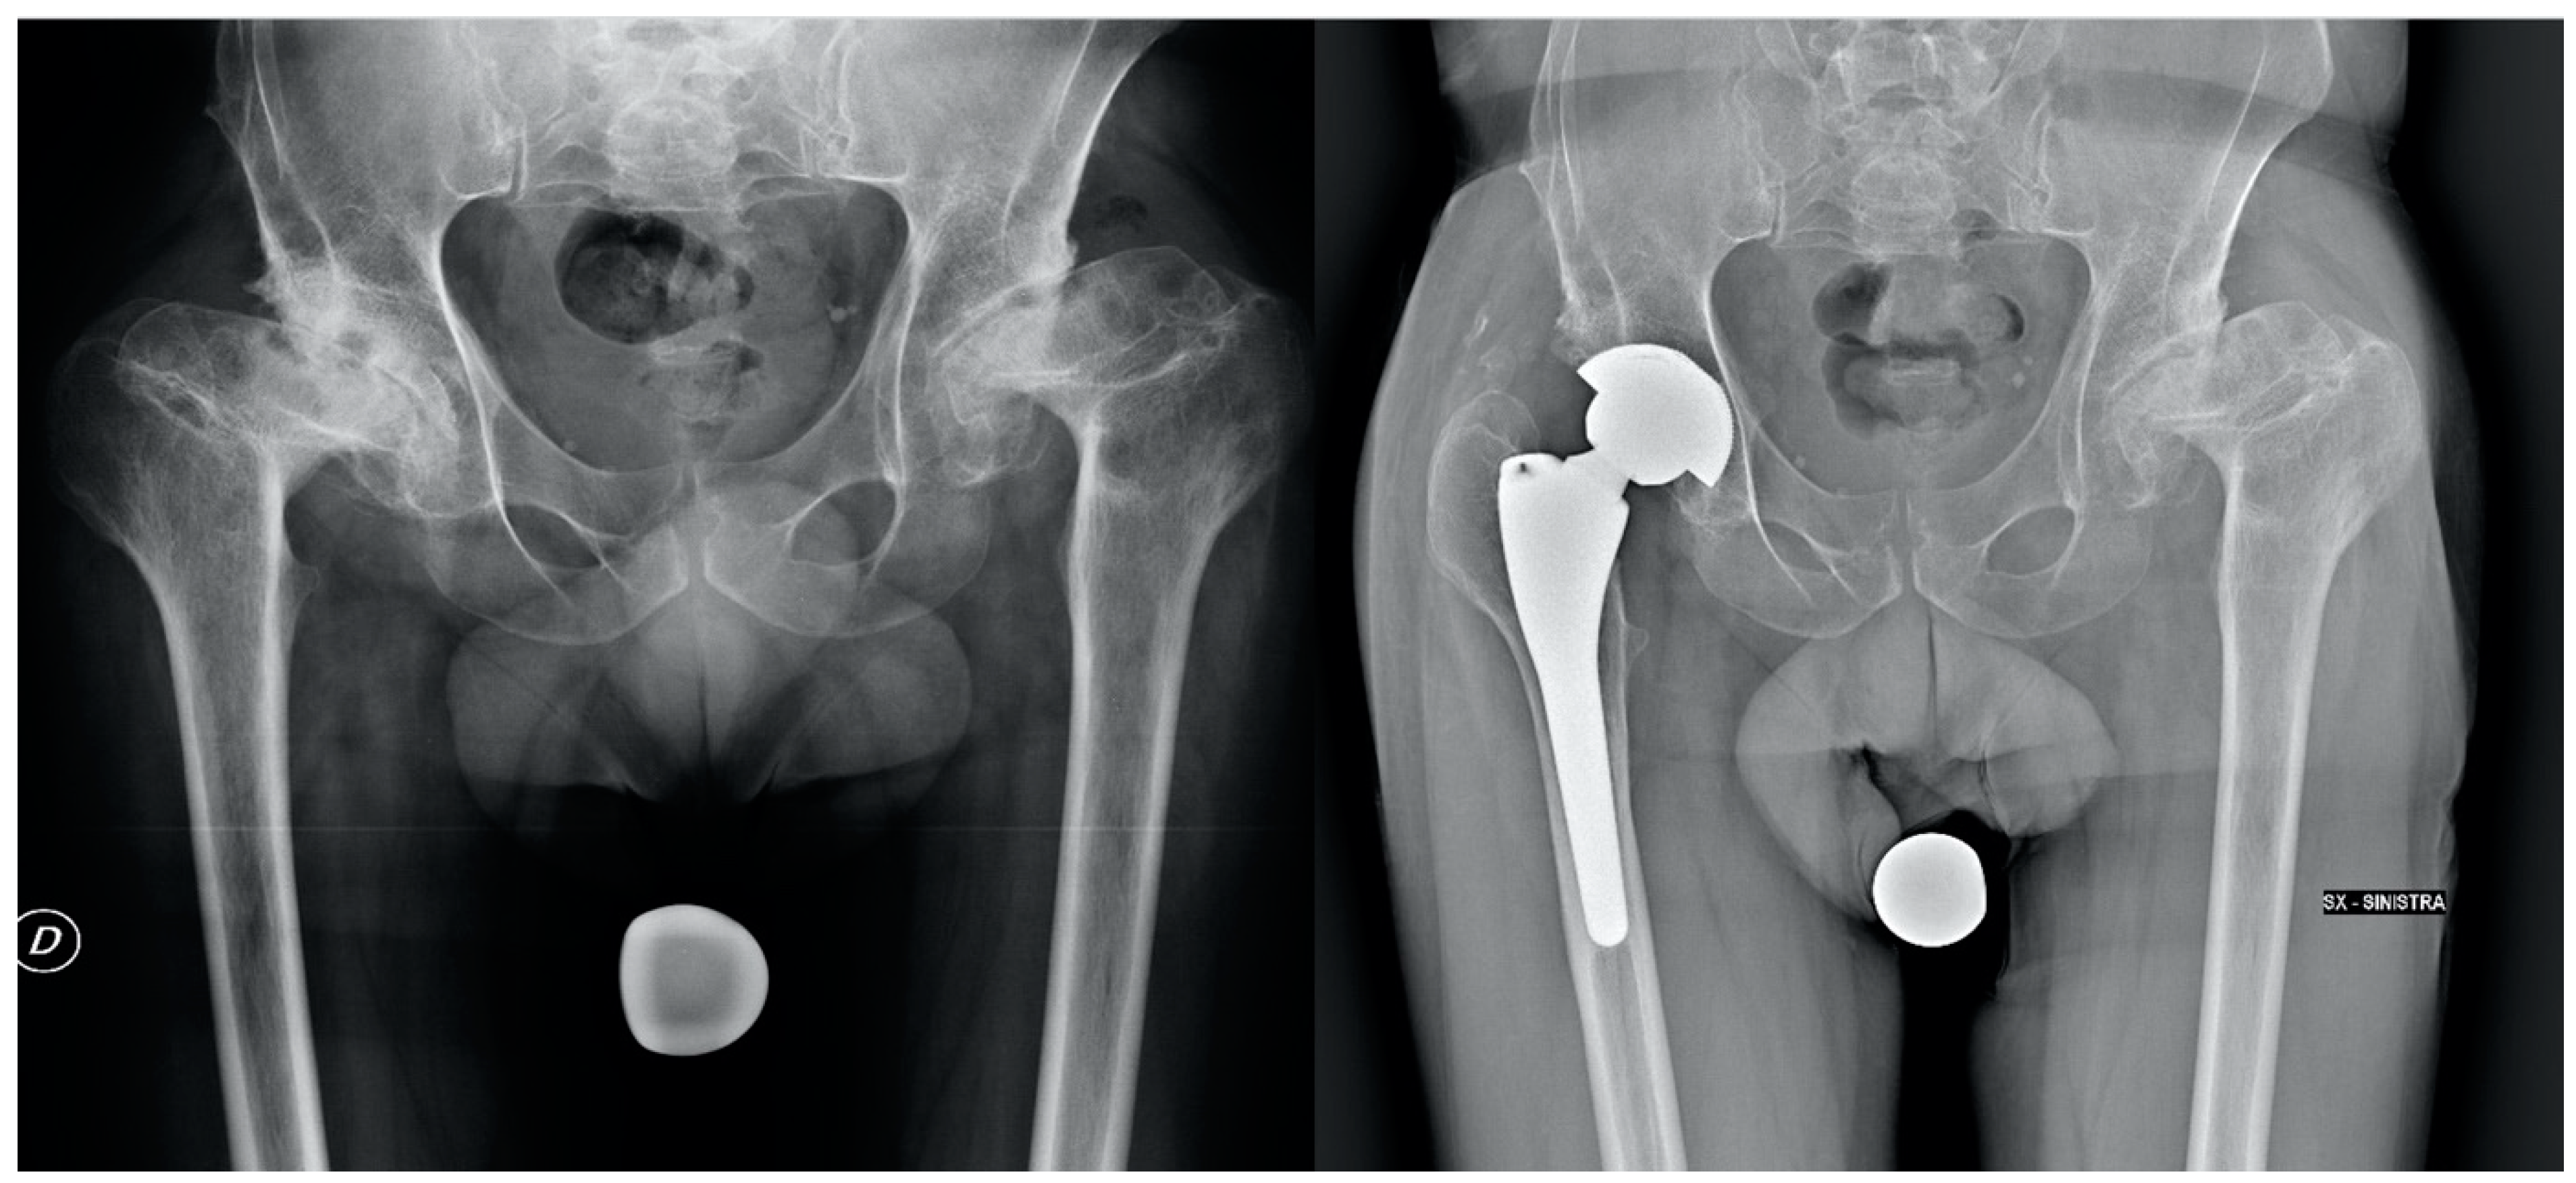

| Pre-operative Crowe classification | I: 26 (65%) II: 14 (35%) |

| Type of stem | Anatomical (Apta Adler Ortho): 16 (40%) Conical (ADR, Smith and Nephew; Wagner Cone, Zimmer; Alata Acuta, Adler): 24 (60%) |